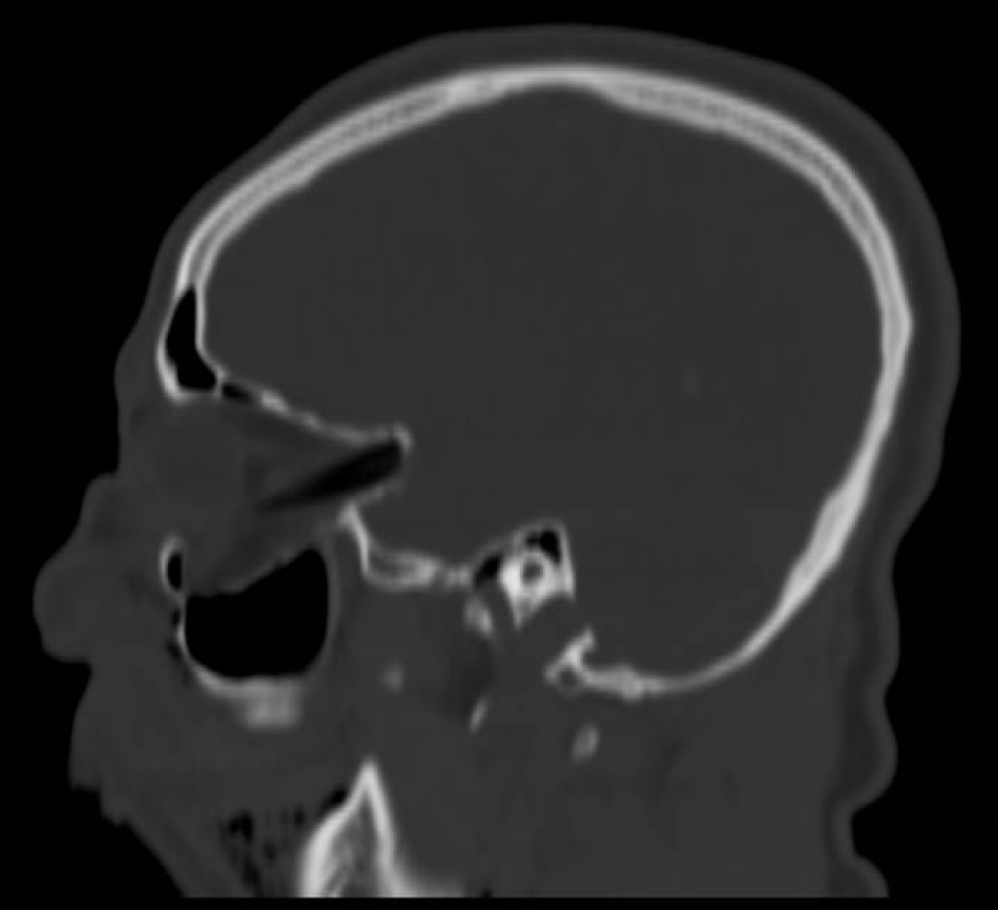

A 25-year-old man was admitted to the emergency room with multi trauma injuries after falling from a second-floor balcony into his neighbor's garden. On arrival, the patient was sedated and placed under artificial respiration. On physical examination, the only external evidence of injury was a 1.5 cm wooden foreign body protruding from the upper lip (Figure 1). Closer examination revealed the foreign body inside the cheek without penetrating the oral cavity. Computed tomography (CT) of the head and face were performed. The images depicted a well formed, radiolucent area with a density similar to that of air in the right orbit. This was later identified as a foreign body penetrating the right orbit in an axial plane from inferior to superior direction. It deflected the globe and penetrated the orbital apex towards the middle cranial fossa to the point of touching but not penetrating the dura mater (Figure 2). A fracture in the floor of the right orbit without the involvement of the lower orbital rim was revealed (Figure 3). Herniation of the inferior Rectus muscle and fat from the orbit into the right maxillary sinus cavity were present (Figure 4). Ocular examination showed no injuries to the globe. The patient received tetanus toxoid and prophylactic intravenous wide spectrum antibiotics. The patient underwent an emergency operation, in the presence of an ophthalmologist and a neurosurgeon. The approach was extra-oral with the aim of exploring and removing the foreign body. The intra-orbital foreign body proved to be a 9 cm bamboo stick (Figure 5). The bamboo stick was meticulously removed. There was no leakage of cerebrospinal fluid (CSF) and no brain tissue was found during exploration examination of the foreign body after its removal. Immediate postoperatively, the patient was transferred to the intensive care. Follow up CT scan demonstrated intact right globe, optic nerve and dura mater. There were no radiolucent findings suggesting that no foreign body remnants were present.

Figure 2: (A, B, C) 3D CT scan demonstrating a foreign body mimicking air in the orbit, deflected the globe and penetrated the orbital apex towards the middle cranial fossa to the point of touching but not penetrating the dura mater. View Figure 2